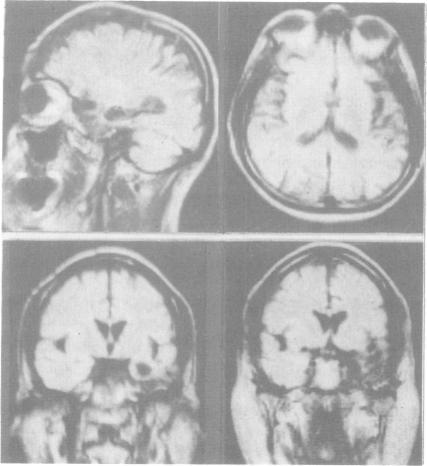

The clinical, neuropsychological and neuroradiological features of two patients affected by herpes simplex virus type 1 (HSV-1) encephalitis are described. An experimental study for the assessment of naming, recognition and description displayed in one patient a persistent significant impairment in naming living things. The other patient showed a failing "semantic memory" for the same categories, although a significant impairment emerged only for plants. In both patients, the late neuroradiological sequelae were localised mainly in the inferior and middle gyri of the left temporal lobe and in the left-side insula. In one patient, the right-side insula was also involved. The selective cerebral damage induced by HSV-1 is stressed and a correlation between the neuroradiological and neuropsychological findings is attempted. The stereotyped anatomical and neuropsychological changes lead to the belief that the virus may recognise, within the limbic system, particular cellular "strains" on the basis of their molecular specificity.

本文描述了两名感染1型单纯疱疹病毒(HSV-1)脑炎患者的临床、神经心理学和神经放射学特征。一项针对一名患者进行的命名、识别和描述能力评估的实验研究显示,该患者在命名生物方面存在持续的显著损伤。另一名患者在相同类别上表现出“语义记忆”衰退,尽管仅在植物方面出现了显著损伤。在两名患者中,晚期神经放射学后遗症主要定位于左颞叶的颞中回和颞下回以及左侧岛叶。在一名患者中,右侧岛叶也受到累及。强调了HSV-1引起的选择性脑损伤,并尝试探讨神经放射学和神经心理学发现之间的相关性。刻板的解剖学和神经心理学变化使人相信,该病毒可能基于分子特异性在边缘系统内识别特定的细胞“株”。